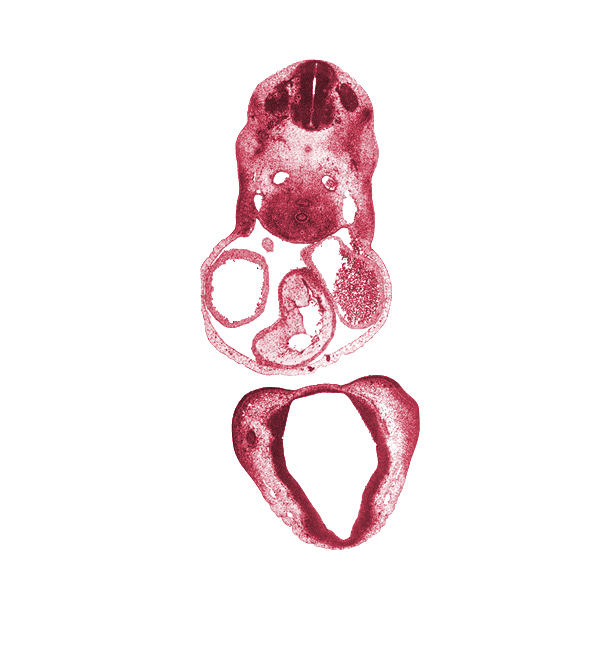

Carnegie Embryo #6502 | Location: 16-04-02

Keywords: C-4 spinal ganglion, alar plate(s), basal plate, cephalic edge of sinus venosus, cerebral primordium (vesicle), cervical plexus, chiasmatic plate, conotruncal ridge(s), conus cordis (outflow tract), corpus striatum, dorsal aorta, edge of optic cup, epithalamus, esophagus primordium, floor plate, left atrium, left precardinal vein, medial nasal prominence(s), notochord, optic groove, pericardial cavity, right atrium, right precardinal vein, roof plate, sulcus limitans, trachea, truncus arteriosus (outflow tract)

Source: The Virtual Human Embryo.